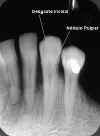

Lesões do Orgão Dentário